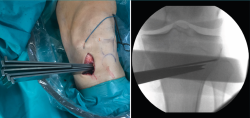

Figura 3. Se marcan los cortes de la osteotomía biplanar con un ángulo de 120°.

Posteriormente, bajo control radioscópico, se realiza la osteotomía apoyando la sierra por debajo de la aguja guía, llegando hasta 1 cm de la cortical lateral. Se introducen los escoplos para abrir la osteotomía (Figura 4). El primer escoplo, el más ancho, se introduce primero para comprobar el corte completo de la cortical posterior. Seguidamente, se coloca el medidor del ángulo de apertura (Figura 5A) y, a continuación, se introduce el distractor en la parte posterior de la osteotomía, evitando así un aumento de la PTP (Figura 5B). En este momento, se puede introducir en la apertura de la osteotomía el aloinjerto o sustituto óseo. Los autores utilizan aloinjerto óseo cuando la apertura es mayor de 10°. Antes de colocar y fijar la placa de osteotomía, se realiza el túnel tibial utilizando las herramientas artroscópicas clásicas (Figuras 6A y 6B). Al realizar una osteotomía biplanar, el corte es suficientemente distal como para permitir brocar el túnel tibial de la RLCA sin dificultades.

Figura 4. Colocación de escoplos de forma progresiva para realizar la apertura (una vez realizados los cortes con la sierra).